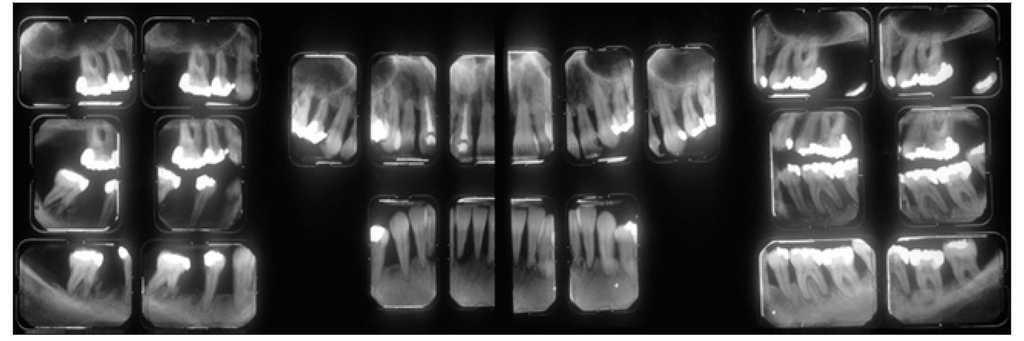

Figura 1 Radiografías periapicales realizadas en 1989 a una mujer de 31 años que muestran una amplia pérdida de hueso vertical como consecuencia de una enfermedad periodontal avanzada.